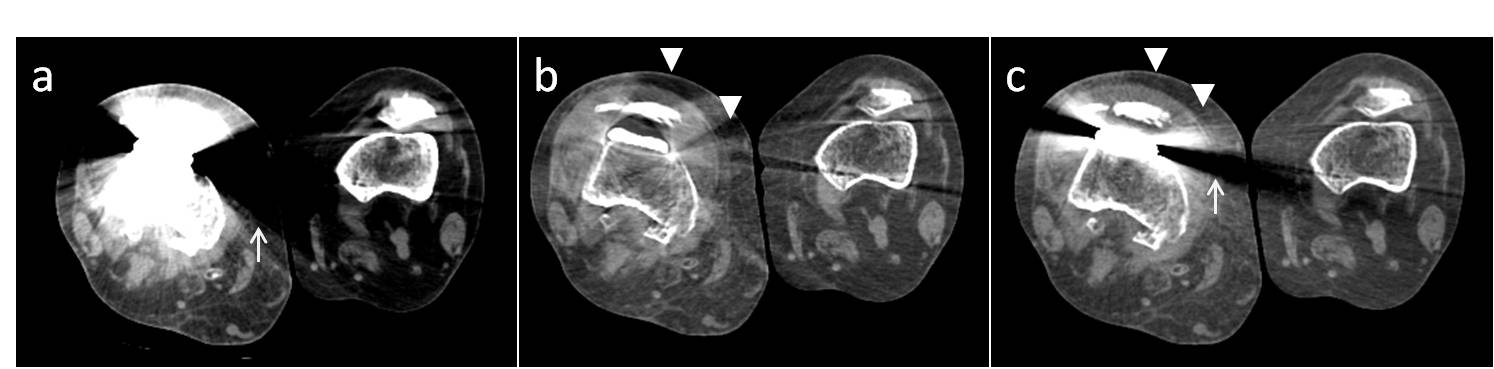

9. Morsbach F, Bickelhaupt S, Wanner GA, Krauss A, Schmidt B, Alkadhi H. Reduction of metal artifacts from hip prostheses on ct images of the pelvis: Value of iterative reconstructions. Radiology. 2013;268:237-244

11. Han SC, Chung YE, Lee YH, Park KK, Kim MJ, Kim KW. Metal artifact reduction software used with abdominopelvic dual-energy ct of patients with metal hip prostheses: Assessment of image quality and clinical feasibility. AJR. American journal of roentgenology. 2014;203:788.

14. Lee YH, Park KK, Song HT, Kim S, Suh JS. Metal artefact reduction in gemstone spectral imaging dual-energy ct with and without metal artefact reduction software. European radiology. 2012;22:1331-1340

15. Lewis M, Reid K, Toms AP. Reducing the effects of metal artefact using high kev monoenergetic reconstruction of dual energy ct (dect) in hip replacements. Skeletal radiology. 2013;42:275-282

17. Guggenberger R, Winklhofer S, Osterhoff G, Wanner GA, Fortunati M, Andreisek G, Alkadhi H, Stolzmann P. Metallic artefact reduction with monoenergetic dual-energy ct: Systematic ex vivo evaluation of posterior spinal fusion implants from various vendors and different spine levels. European radiology. 2012;22:2357-2364